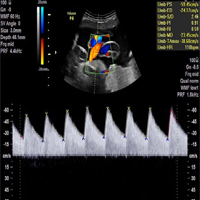

Ultrasound produces very precise images of your soft tissues (heart, blood vessels, uterus, bladder, etc.) and reveals internal motion such as heart beat and blood flow. It can detect diseased or damaged tissues, locate abnormal growths and identify a wide variety of changing conditions, which enable your doctor to make a quick and accurate diagnosis.

• Whole Body Colour Doppler